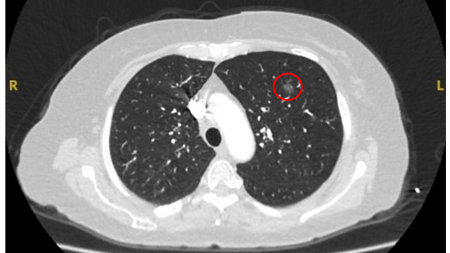

Ground-glass nodules: growth of 2 mm in maximum diameter should be considered potentially significant, while the development of a solid component suggests that further investigation and/or treatment should be considered.[Figure caption and citation for the preceding image starts]: Computed tomography (CT) showing a left upper lobe ground-glass nodule. This was eventually resected 2 years into surveillance because of growth and the histopathology confirmed adenocarcinoma of lung with mixed mucinous-lepidic patternFrom the collection of Dr George Tsaknis, MD, PhD, FRCP(London), MRQA, MAcadMEd, PGCert; used with permission [Citation ends].